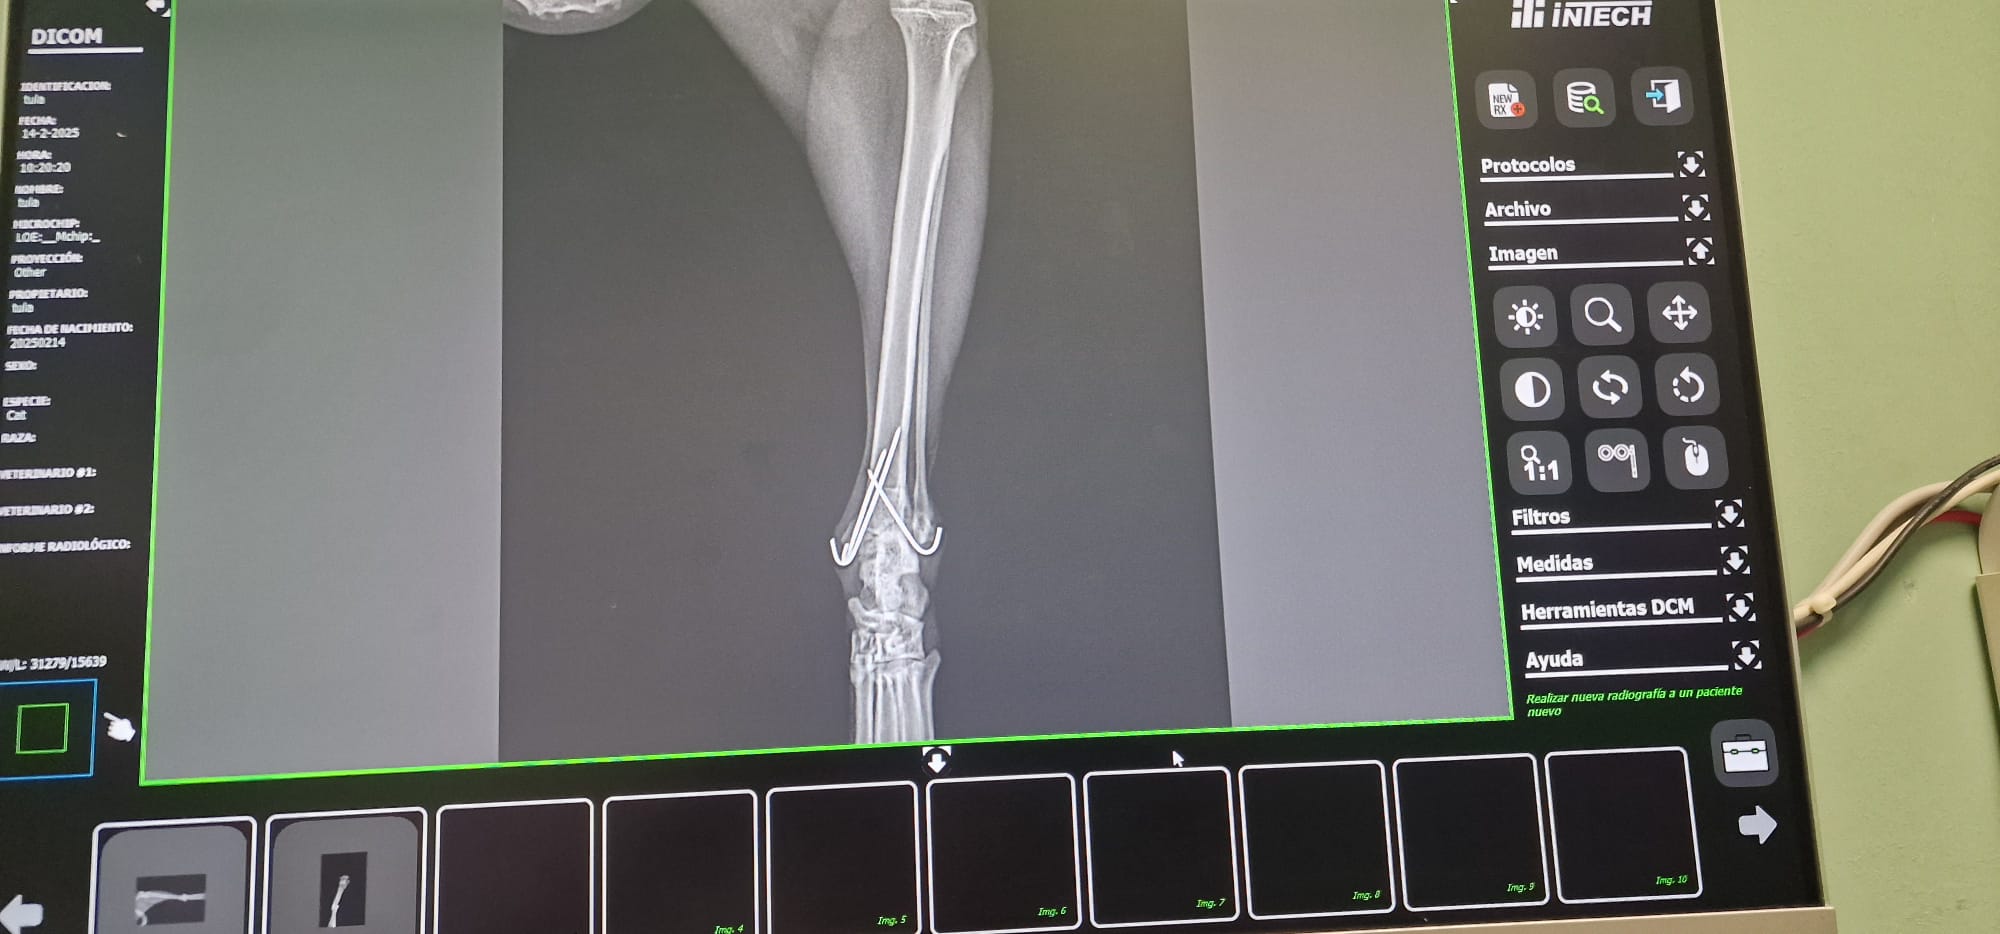

Radiografías = Salud en Imágenes 🐾🩺En Smile Vet, ofrecemos servicios de radiografías para cuidar la salud de tu mascota con precisión y cariño.

• Diagnóstico Rápido: Las radiografías nos permiten detectar problemas (óseos, dentales, respiratorios, cardiacos, etc.) y cuerpos extraños sin procedimientos invasivos. 🐶🐱

• Tecnología Avanzada: Utilizamos equipos modernos para obtener imágenes claras y detalladas, asegurando un diagnóstico eficaz.

• Cuidado Integral: Nuestro equipo interpreta los resultados para ofrecerte el mejor plan de tratamiento, siempre con el bienestar de tu mascota como prioridad. 🐾